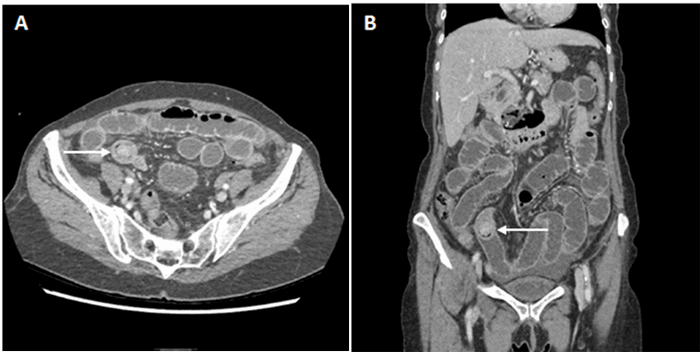

A 69-year-old female with no significant medical history presented with three days of episodic abdominal pain after oral intake, emesis, and obstipation. The patient denied any history of prior gallbladder disease, abdominal surgeries, or medication use. On physical exam, there was generalized tenderness to palpation, worst in her epigastrium. An abdominopelvic CT (Figure 1) demonstrated dilated small bowel loops with a well-defined, calcified lesion in the distal ileum. The common bile duct was dilated to 9 mm, and a cholecystoduodenal or choledochoduodenal fistula was suspected.

Figure 1. Computed tomography of abdomen pelvis with contrast. A) Axial section demonstrating gallstone (arrow) in distal ileum. B) Coronal section demonstrating calcification and gallstone with transition point at distal ileum.